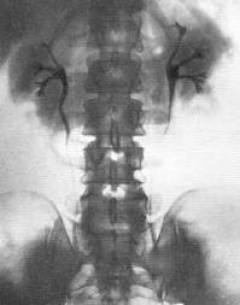

Экскреторная урография

- Уменьшение объема почки и коркового вещества.

Экскреторная урография почек

Метод основан на способности почек выделять рентгеноконтрастные вещества с йодом, вводимые внутривенно. На рентгеновских снимках, сделанных через определенные интервалы, отображаются почки и мочевыводящие пути.

При нефросклерозе фиксируется уменьшение объема почки и коркового вещества, а также отложения кальция (нефрокальциноз).